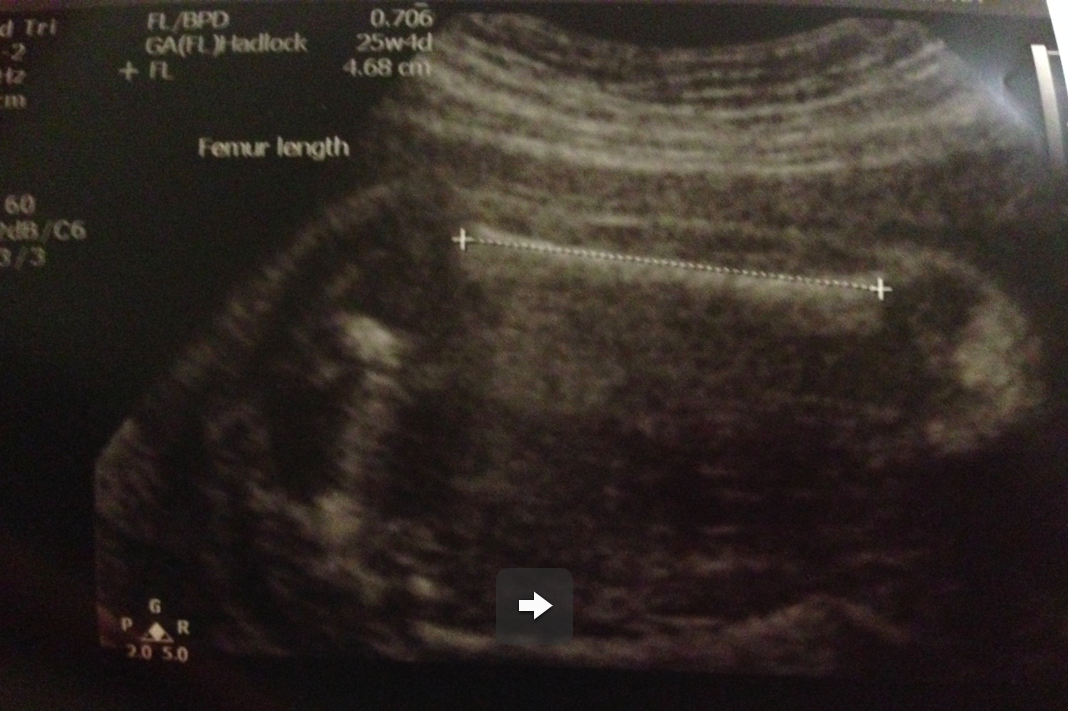

大脾骨長~

如果大家有仔細睇超聲波相上面嘅small prints就會見到correlated嘅週數,當然呢個reference係外國B啦,但都同我哋亞洲B唔會差得太遠,三樣measurement都係正負一週之內,非常好,BB呱叻叻﹗﹗